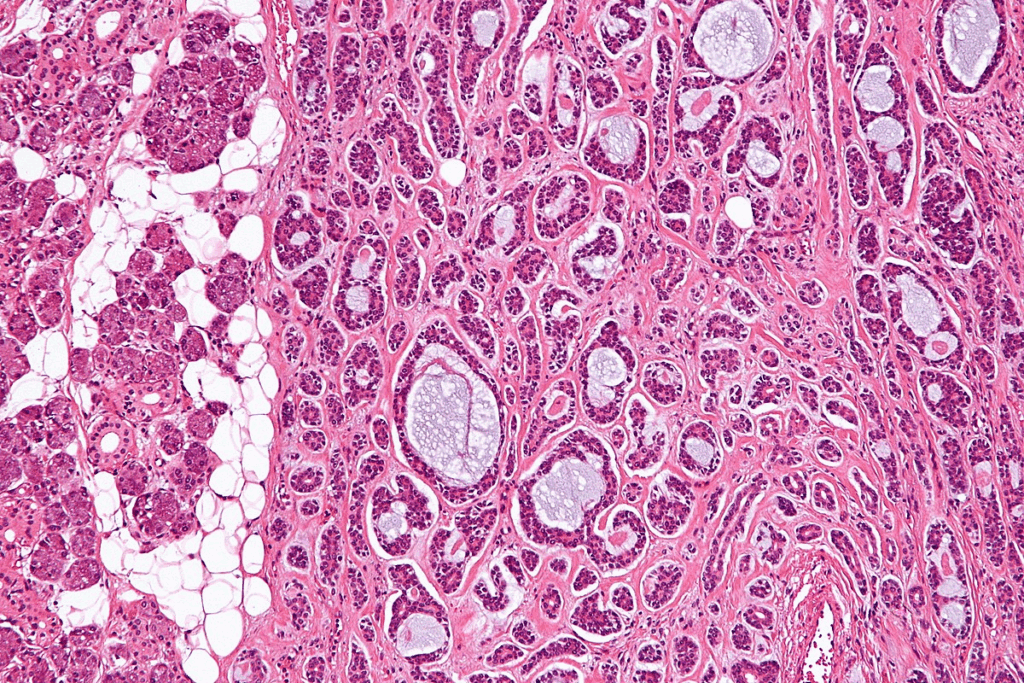

Adenoids are gland-like tissues that are key to our immune system. They sit at the back of our throat. They help catch pathogens, supporting our body’s fight against infections.

When adenoids grow too big, it can cause health problems. It’s important to know how adenoids work and how they affect our health.

- Adenoids are part of the lymphatic system and help fight infection.

Adenoids are a key part of the immune system, mainly in kids. They are found at the back of the throat and look like glands. They help catch germs that come in through the nose and mouth, keeping infections away.

But, if adenoids get too big, they can block breathing and cause other problems. It’s important to know about adenoids and how they work. This is true, even more so for kids. Getting regular check-ups with a doctor can spot adenoid issues early.

Adenoids are gland-like tissues at the back of the throat. They help the immune system, mainly in kids. But when they grow too big, they can block breathing, cause ear infections, and disrupt sleep.

Adenoids are gland-like tissues at the back of the throat. They are above the roof of the mouth. They help fight infections and are part of the lymphatic system.